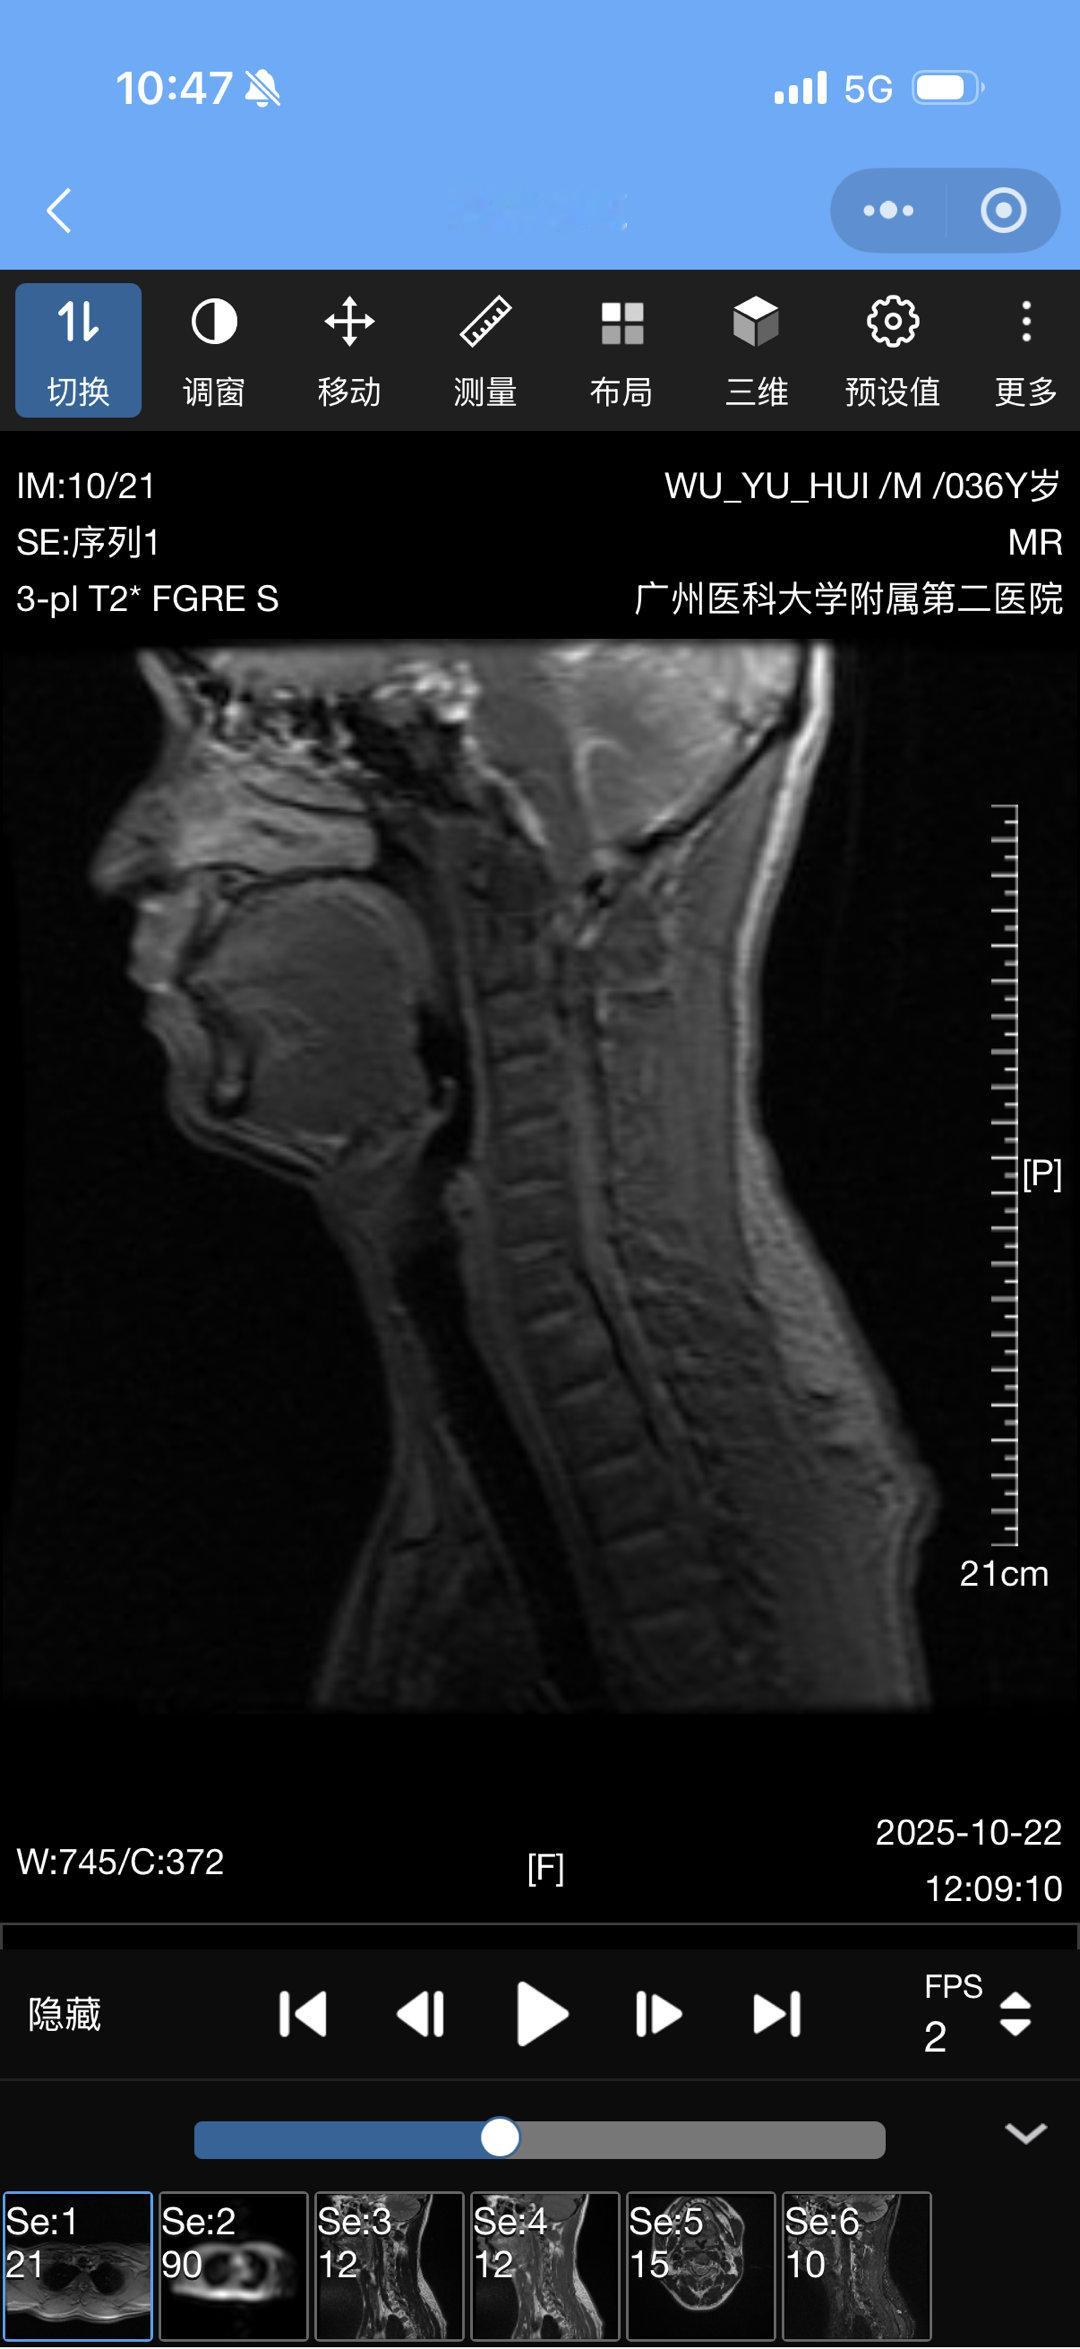

结果出来了颈椎间盘4 节突出还有救吗[捂嘴哭]幕后工作十几年的代价

结果出来了

颈椎间盘4 节突出

还有救吗[捂嘴哭]

幕后工作十几年的代价